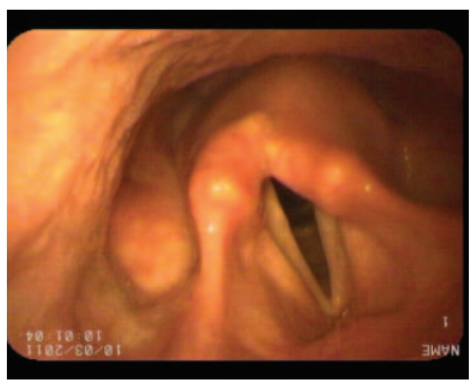

Hình ảnh nội soi mũi họng ống mềm của dây thanh ở một người đàn ông 45 tuổi có giọng nói yếu. Bạn đã yêu cầu ông ấy cố gắng phát âm